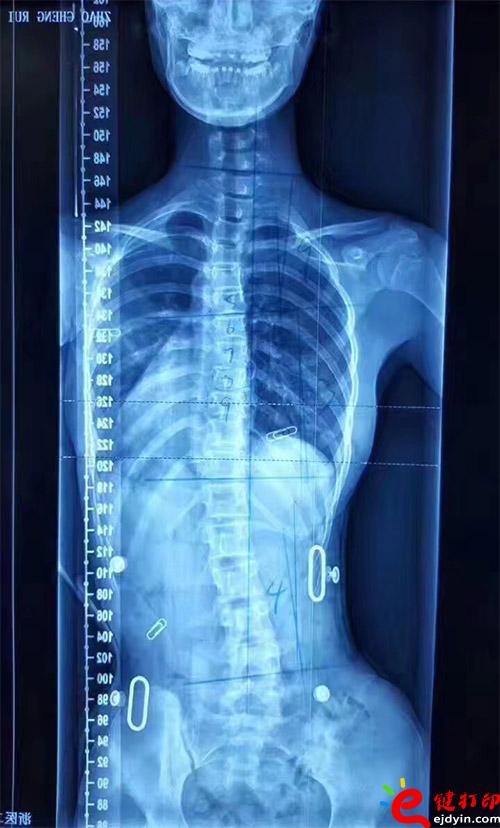

在脊柱側彎患者中,僅有10%的青少年特發性脊柱側彎患者最終需要手術治療,90%的患者可以保守治療和積極觀察。非手術治療中公認最主要和可靠的方式是用矯形支具治療。像上圖這樣的案例就可以通過矯形器治療。每個人的畸形不一樣,就需要像3D打印這樣可定制又便宜的技術幫助。